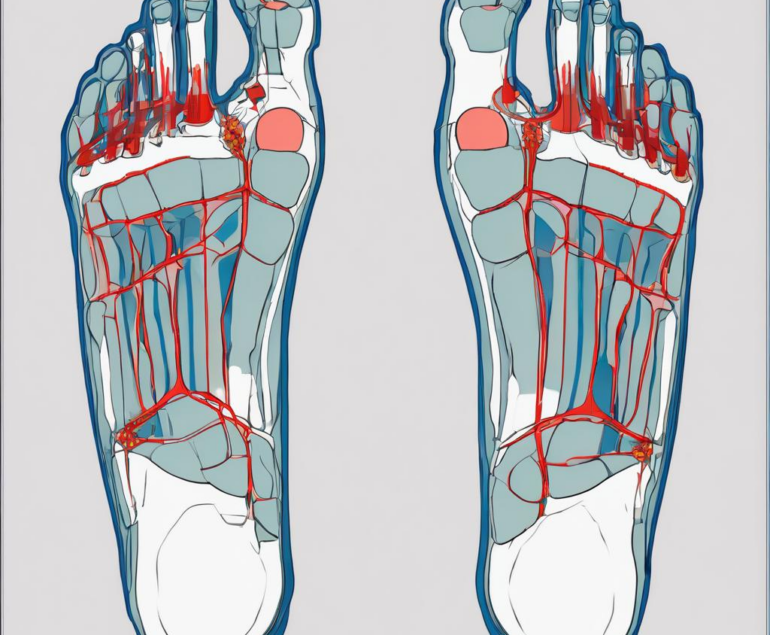

Die Iontophorese am Fuß reduziert übermäßiges Schwitzen durch gezielte Abgabe ionisierter Substanzen. In diesem Beitrag erläutere ich für Sie Wirkmechanismen, Indikationen und praktische Anwendung.